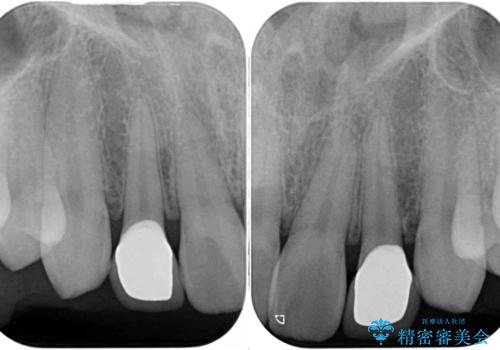

- 前歯のラミネートベニアの不自然な色合いを気にして来院された患者様です。

矯正治療後戻り防止のワイヤー周りにむし歯があったため、オールセラミッククラウンにて補綴することとしました。